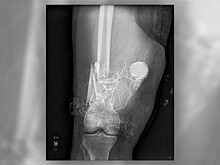

Хирурги удалили из бедра неразорвавшийся заряд фейерверка

Новости

27 февраля 2018